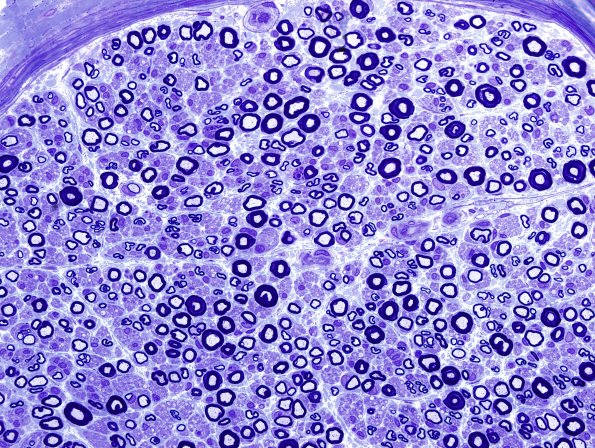

Washington University Experience | PERIPHERAL NEUROPATHY | 6 AXONAL DEMYELINATION (BASIC PROCESS) | 6A1 Demyelination (Case 6) Plastic 1.jpg

6A1,2 Plastic sections of a nerve illustrating scattered demyelinated axons. (Toluidine blue stained one micron thick plastic sections)